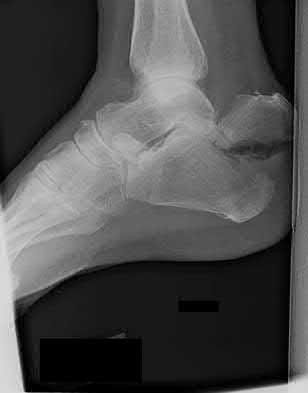

2. # A 35-year-old woman is involved in a head-on collision while driving. Initial radiographs are shown in Figures 8a and 8b. Injury to what vessel increases the risk for osteonecrosis of the injured bone?

1. Dorsalis pedis artery

2. Perforating peroneal artery

3. Lateral tarsal artery

4. Artery of the tarsal canal

5. Artery of the tarsal sinus Corrent answer: 4

The patient has a Hawkins type III talar neck fracture-dislocation with a risk of osteonecrosis ranging from 69% to 100%. Anatomic studies have shown that the artery of the tarsal canal supplies the lateral two thirds of the talar body.

The other vessels listed provide no significant contribution to the talus.